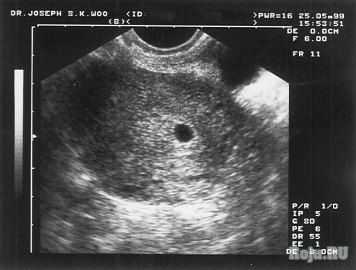

Замершая беременность у каждой второй девушки? Не верю! Не уже ли в 21 веке нельзя найти лекарство, которое спасало бы наших малышей?!

У меня тоже была первая беременность замерзая, при этом абортов не было.

Это естественный отбор! Значит нужно так! И у меня была зб, а сейчас двое пацанов) все норм